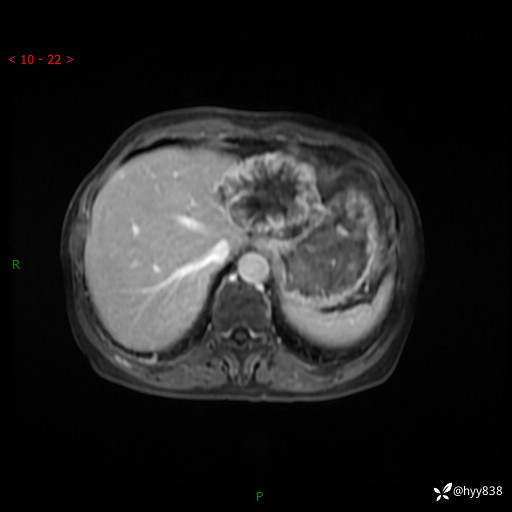

老年女性,偶然发现肝脏占位,综合各个序列,你考虑什么---结果公布

患者年龄:66岁

主诉:发现肝脏占位性病变2天

简要病史:患者2天前因“腰疼”至当地医院就诊时发现肝脏左叶占位性病变,无发热、畏寒,无皮肤黄染,无腹痛、腹泻,无恶心、呕吐、厌油等不适,今进一步诊治遂来我院就诊,门诊以“肝脏占位性病变性质待查”收入我科。 起病以来,患者精神、睡眠一般,饮食欠佳,二便正常,体力、体重无明显减轻,

辅助检查:MRI

临床诊断:肝占位

肝脏MRI平扫(同反相位)

T2WIfs+DWI

增强(动脉期+静脉期+延迟期)